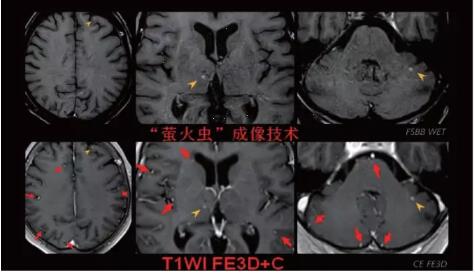

見所未見 微小腫瘤無處遁藏——

“螢火蟲”成像技術 顱內腫瘤微小病灶檢出新發(fā)現

此技術主要用于神經系統(tǒng)惡性腫瘤,以及其他腫瘤腦轉移瘤篩查。傳統(tǒng)情況下做腫瘤腦轉移篩查,很容易漏掉5mm以下小病灶,臨床發(fā)現后干預治療比較晚,要實現2mm高空間分辨率和超薄層全腦掃描在保證信噪比的情況下需要很長時間大概十多分鐘,而且薄層增強序列顱內血管呈高亮信號,會干擾顱內小病灶的觀察,血管和小病灶區(qū)分困難。佳能”螢火蟲”成像技術既可以實現高空間分辨率和超薄層(最薄可實現0.2mm)全腦掃描,掃描時間短,2-3分鐘即可實現全腦3D掃描,同時避免了血管高亮信號的干擾,對顱內原發(fā)或繼發(fā)的微小腫瘤檢查有重大意義。“螢火蟲”成像技術具有磁敏感效應,對于亞急性血敏感敏感,可以區(qū)分出血和強化的腫瘤。